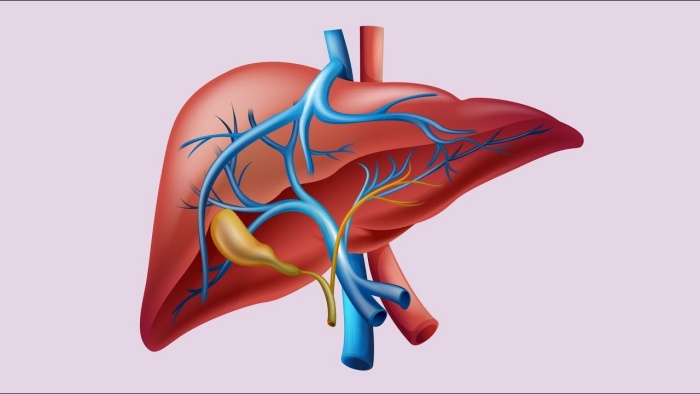

Her insanın sağlığı ve esenliği, vücudunun toksinleri ne kadar iyi atıp temizlediğine bağlıdır. Çevresel toksinlere, toksik vücut bakım ürünlerine ve işlenmiş gıdalara maruz kalan çoğu insan, ciddi bir detoksa umutsuzca ihtiyaç duyuyor! Vücudun toksinlerden kurtulmasının ana yollarından biri karaciğerdir. Aslında karaciğer vücudun en çok çalışan organlarından biridir. Kanımızı detoksifiye etmek, yağları sindirmek için gereken safrayı üretmek, hormonları parçalamak ve gerekli vitaminleri, mineralleri ve demiri depolamak için yorulmadan çalışır. Karaciğer fonksiyonu optimal olmadığında, yiyeceklerimizi, özellikle de yağları düzgün bir şekilde sindiremeyiz. Bu nedenle karaciğer yağlanmasından kaçınmak ve toksinleri vücuttan atmak için karaciğeri temizleyen bir diyet uygulamak çok önemlidir.

Karaciğer Ne Yapar?

Karaciğerin temel işlevlerinden bazıları şunlardır:

• Bağırsaklar tarafından emilen besin maddelerinin işlenmesi, böylece daha verimli emilmeleri sağlanır

• Protein, yağ ve şekeri dengelemek için kan bileşimini düzenlemek

• Eski kırmızı kan hücrelerinin yok edilmesi

• Kanın düzgün bir şekilde pıhtılaşmasına yardımcı olmak için gerekli kimyasalları üretmek

• Alkol ve ilaçları parçalamak ve metabolize etmek

• Temel proteinleri ve kolesterolü üretmek

• Bilirubin, amonyak ve diğerleri dahil olmak üzere toksinleri kan dolaşımından uzaklaştırmak

• Minerallerin, demirin ve A vitamininin depolanması